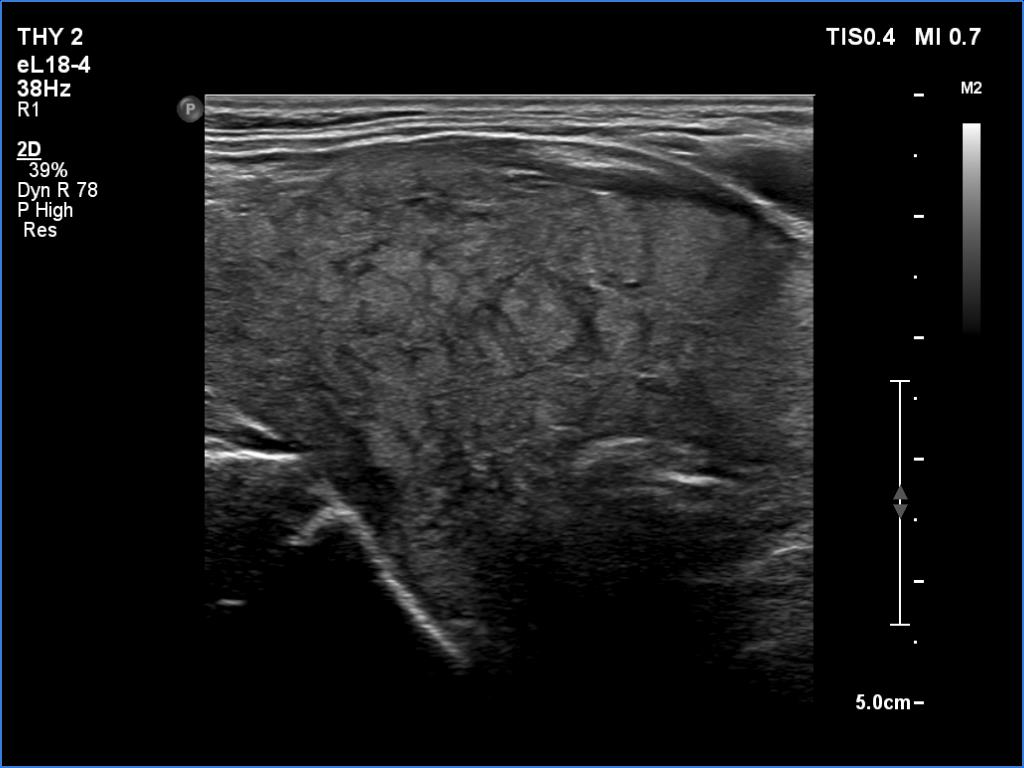

Second examination 6 years later (second row of images):

Clinical data: The patient was referred for a follow-up.

Palpation: unchanged.

Laboratory tests: TSH 3.52 mIU/L.

Ultrasonography. The pattern was the same as in the previous study except for the lesion in the isthmus which has been increased in size.

Suggestion: TSH in a year, ultrasound in 3 years.

Comment. This is the typical presentation of the micronodular form of Hashimoto's thyroiditis.